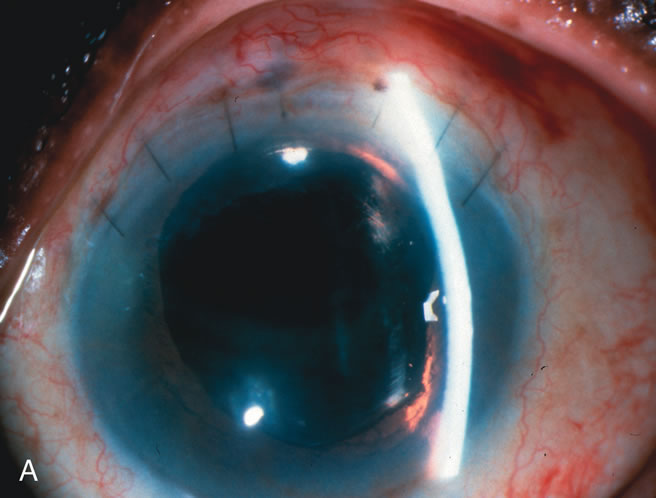

In years past, patients with both cataract and glaucoma frequently provided overwhelming surgical challenges for the ophthalmologist. The ability to carry out phacoemulsification through a 3.2-mm corneal incision along with inserting a foldable IOL is a vast improvement over 11-mm incisions that were common a decade ago (Fig. 1). The anatomical and inflammatory changes to the eye are less with small incision techniques, improving the likelihood of success with concomitant glaucoma surgery. Pharmacologic inhibition of fibrosis along with postoperative wound revision increases the long-term success rate of filtration surgery when combined with lens extraction. (Fig. 2). The learning curve may be steep at times, but the blending of cataract and glaucoma surgical skills slowly falls into place as the surgeon constantly learns and upgrades his or her technique.

Fig. 1. The anatomic advantage of small incision cataract surgery for the glaucoma patient. A. Long-term bleb function with a large cataract incision is difficult to achieve with either ECCE-trabeculectomy or trabeculectomy followed later by ECCE. This bleb failed to form sufficiently when combined with large incision ECCE. The inflammation, bleeding, and long-term wound healing with stimulation of fibroblasts associated with this technique are more likely to cause bleb failure. In addition, the increased iris manipulation necessary to deliver the nucleus and subsequent iris repair adds to the long-term breakdown of the blood aqueous barrier. B and C. Two-site phacotrabeculectomy has the advantage of small incision cataract surgery combined with separate site trabeculectomy. The incision size is one third the size of the standard ECCE. The inflammation is less severe, and cataract wound healing is confined to the temporal area. Visual rehabilitation with phacoemulsification and foldable IOL is much faster. Phacoemulsification allows successful lens extraction even in the unfriendly environment of a smaller pupil compared with ECCE. The trabeculectomy is performed in an entirely different site, well away from the wound healing associated with temporal phacoemulsification. The likelihood of this filter functioning long-term is greater than with ECCE-trabeculectomy. D. The surgeon also has the option of single-site phacotrabeculectomy with foldable IOL. Both the lens extraction and trabeculectomy are performed through one small 3.5-mm limbal incision.